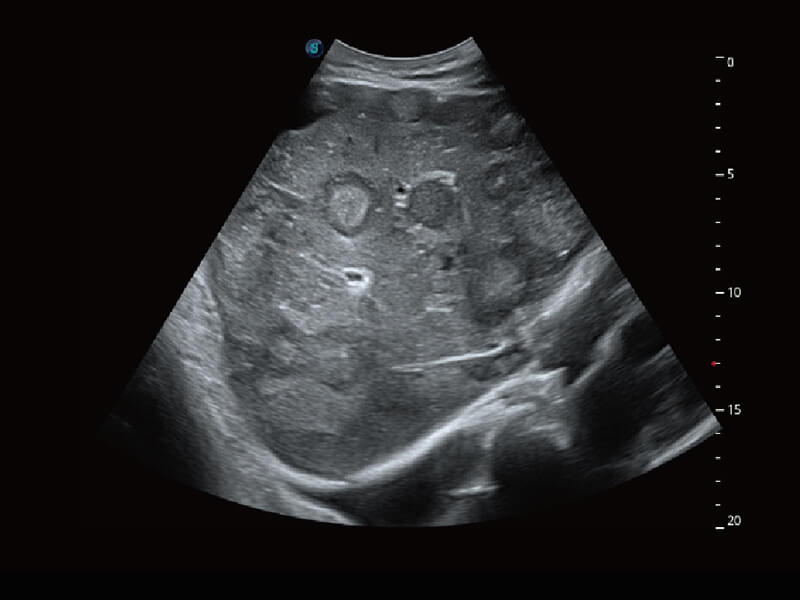

S60探头工艺,从前端信号处理每一个环节采集无损声学数据,真实还原组织原貌,再现解剖细节。

性能优异的硬件架构,极大提升超声系统的运行效率和数据处理能力。相比以往超声成像系统,Wis+平台为您带来极快的响应速度和成像帧频,提升检查流畅度。